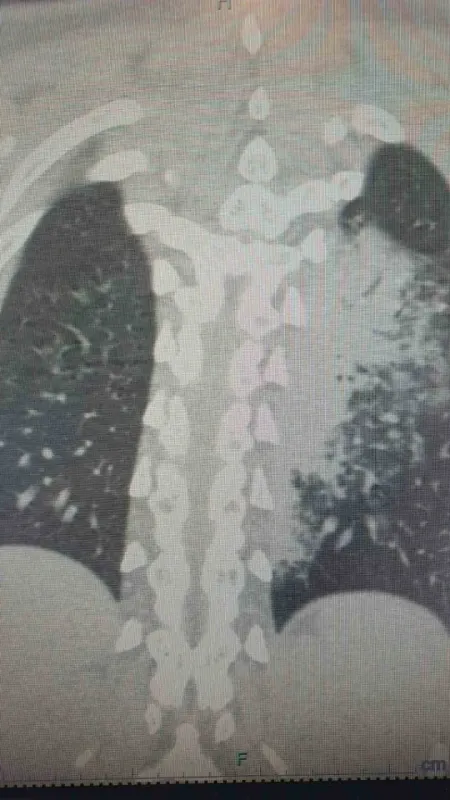

Göğüs Hastalıkları Uzmanı Prof. Dr. Şevket Özkaya, özellikle otel ve tatil köylerinde konaklayan kişiler arasında “beni klima çarptı” diyen neredeyse her iki kişiden birinde bu hastalıkların saptandığını belirtti. Prof. Dr. Özkaya, bu durumdan en çok etkilenenlerin ise çocuk yaş grubu olduğunu vurgulayarak, “Ciddi sayıda, daha önce görülmemiş derecede çocuk bronşiti ve zatürresi vakaları görmeye başladık. Hatta COVID-19 salgınında, çocuk yaş grubunda COVID-19 virüsüne bağlı bu kadar çok zatürre görmüyorduk. Son günlerde; ‘Legionella’ bakterisinin, çocuk yaş grubunda COVID-19’a oranla çok daha fazla zatürreye neden olduğunu görüyoruz” diye konuştu.

Legionella pneumophila isimli bakterinin klimalardan üremesi sonucunda hastalığın ortaya çıktığını belirten Prof. Dr. Özkaya, bu hastalığın kronik rahatsızlığı olanlarda ölümcül olabileceğini ve yaşlı, kronik hastalığı olan vatandaşların dikkatli olmaları gerektiğini hatırlattı.

Özellikle klimaların iyi temizlenmesi gerektiğini belirten Prof. Dr. Özkaya, klima zatürresinde şikayetlerin daha az olduğu için grip gibi eklem ağrıları, ateş, halsizlik, ishal gibi hafif soğuk algınlığı belirtileriyle seyrettiği için çok fazla anlaşılmayabileceğini söyledi. Kronik hastalığı olanlarda hayati sonuçlar da doğurabileceğini belirten Özkaya, “Pandeminin bitmesiyle beraber ani ısı değişikliklerine, soğuktan sıcağa geçişlere ve klimalara maruz kalmak, grip ile karıştırılabilir ve önemsenmeyebilir. Çocuklar ise ne hissettiklerini anlatamadıkları için uzamış öksürük ve ateş şikayeti ile doktora başvurduklarında ciddi zatürre vakaları ile karşı karşıya kalırlar” dedi.